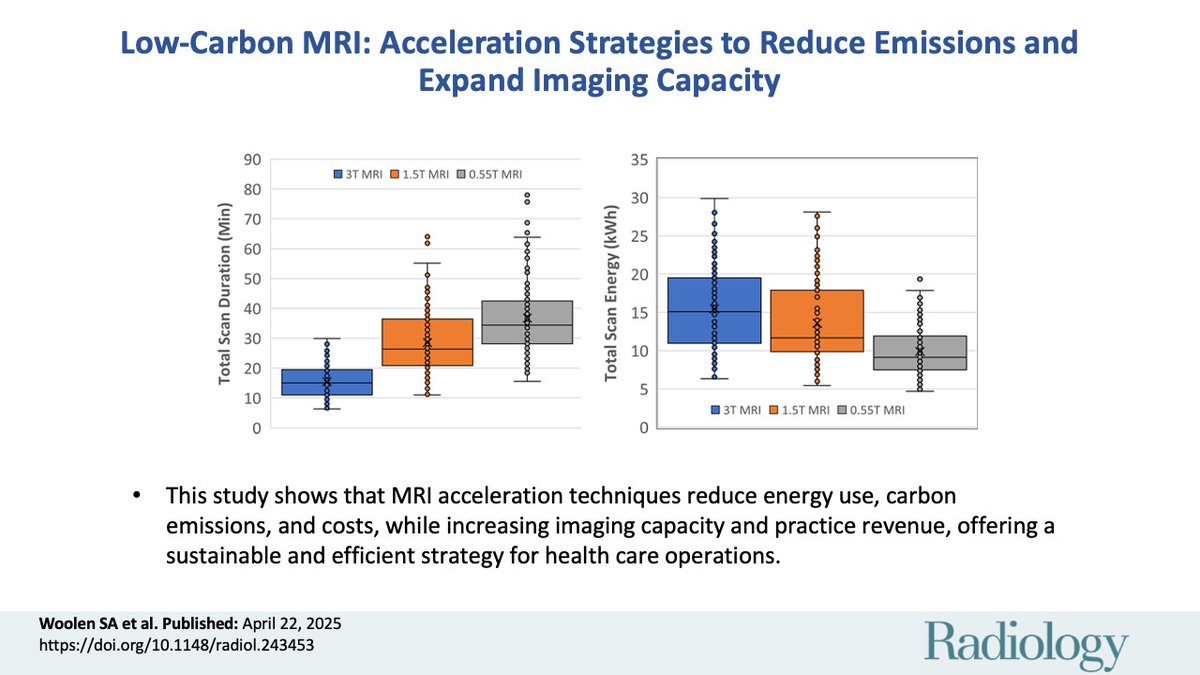

Can faster MRI be greener too? 🌍🧠 This study by Sean Woolen MD MS Kate Hanneman Susie Huang Azadeh Tabari Jan Vosshenrich, MD shows how acceleration cuts energy use, emissions, and costs, while boosting capacity. A smart, sustainable win! #LowCarbonMRI #Radiology pubs.rsna.org/doi/10.1148/ra…

Woolen et al measured the energy expenditures during specific MRI protocols on different field-strength magnets. Read on to see the results! #RadGoesGreen UCSF Imaging Sean Woolen MD MS Kate Hanneman Susie Huang Azadeh Tabari Jan Vosshenrich, MD Christopher Hess bit.ly/4jGof2n